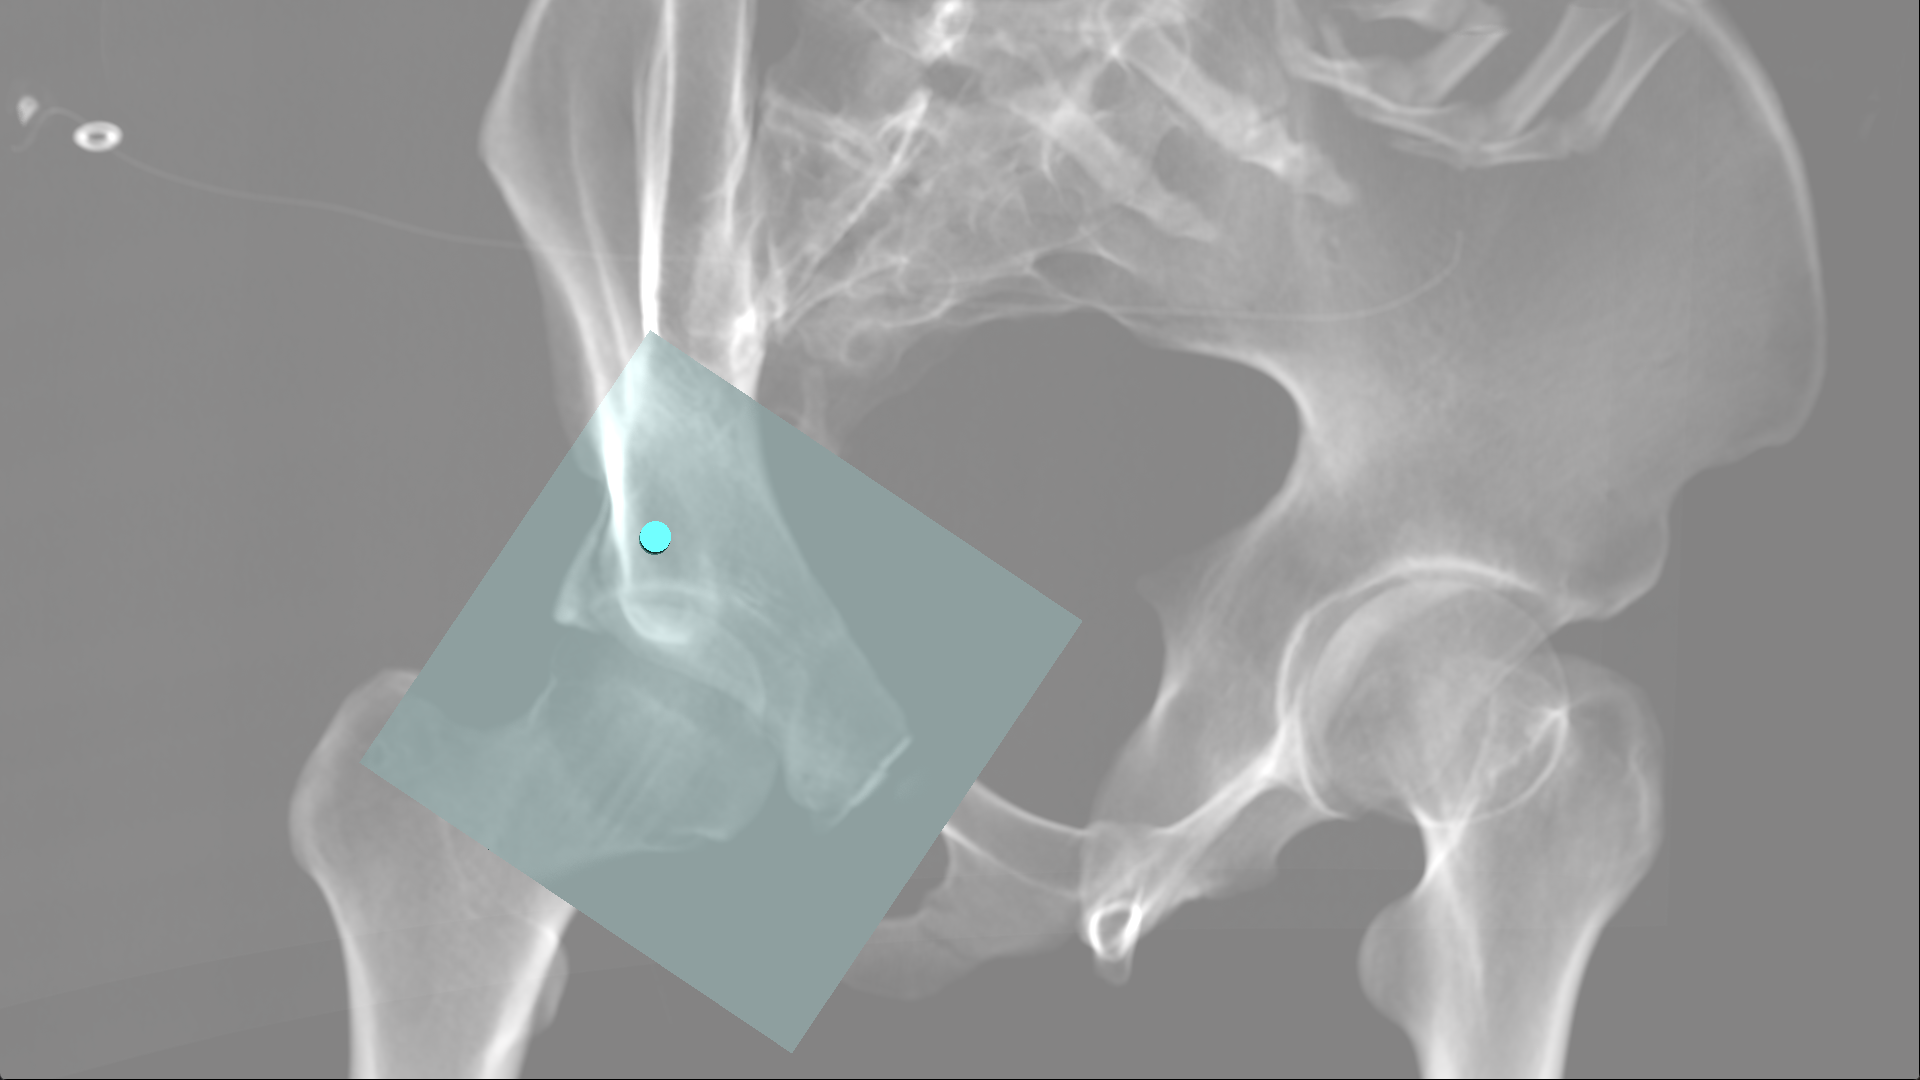

术中的操作图片.png

手术过程中通过混合现实设备观察到的螺钉和骨折位置